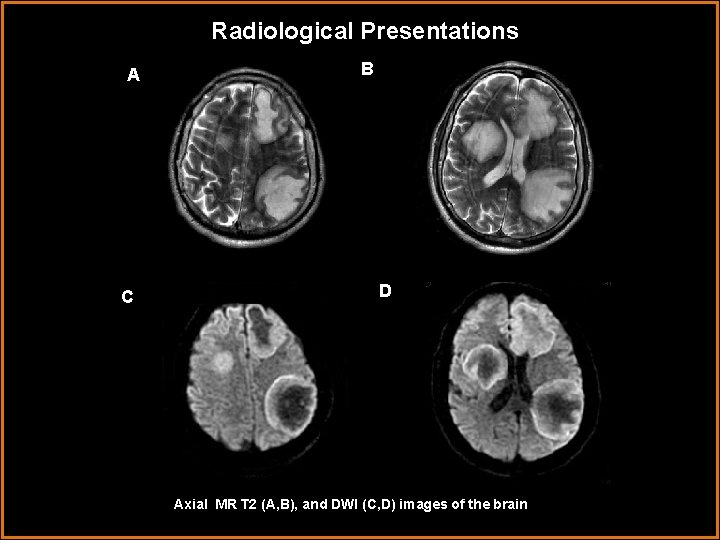

Radiological Presentations A C B D Axial MR T 2 (A, B), and DWI (C, D) images of the brain

Radiological Presentations A C B D (A, B) Axial MR T 2 images demonstrate T 2 hyperintense lesions which do not exert significant mass effect on the surrounding parenchyma. (C, D) Axial DWI images demonstrate rim of restricted diffusion surrounding the lesions